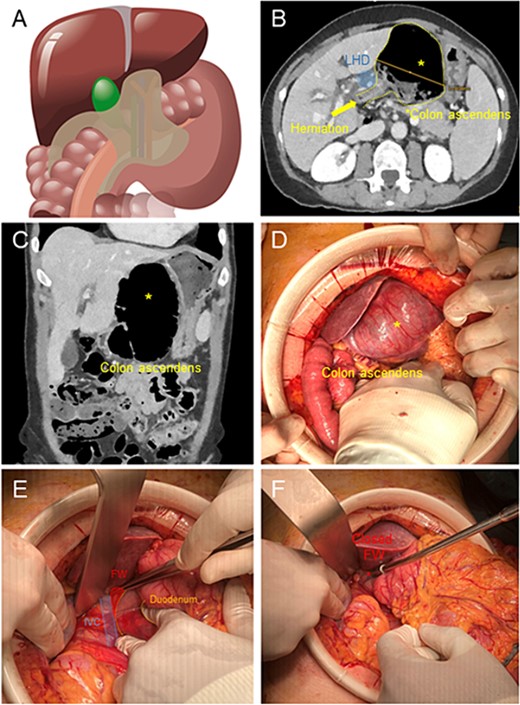

(A) Illustration of cecal herniation through WF as shown in CT scan. (B) Dilated colon ascendens behind the Ligamentum Hepatoduodenale (LHD) in the CT Scan. (C) The coronary view shows the dilated colon. (D) Intraoperative hernia presentation after laparotomy, the dilated colon presents a serosal tear (*) in its surface. (E) After reduction of hernia, exposure of WF, with inferior vena cava below and Duodenum to the right. (F) Closure of WF with interrupted suture with p-Dioxanon (PDS 4-0).

We performed a 12-cm laparotomy, which allowed us to confirm the diagnosis (Fig. 1D). We incised the thin lesser sac, performed a manual derotation of the cecum and cautiously successfully pulled laterally the herniated viscera through the WF (Fig. 1E). The cecum appeared massively dilated with serosal tears. The whole ascending colon appeared lax and hypermobile. Therefore we performed a right hemicolectomy with a stapled side-to-side ileo-colic anastomosis and mesenterial closure. To prevent the recurrence of visceral herniation through the WF, we applied two simple stitches in PDS 4.0 in the inferior portion of the WF aiming to restore its normal diameter (Fig. 1F).